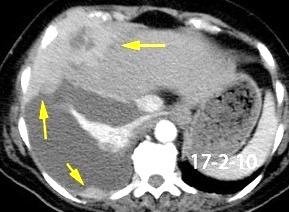

Absceso secundario a perforación de carcinoma. 3-4%. En flexura esplénica puede tener absceso subfrénico o empiema.

Empiema pleural secundario a carcinoma de la flexura esplénica (masa visible)

Lian R et al. Empyema caused by a colopleural fistula. Medicine (Baltimore) 2017/Osada T,, et al. Thoracic empyema associated with recurrent colon cancer: report of a case and review of the literature. Dis Colon Rectum 2001

Comunica con el hiato esofágico y el espacio pararrenal anterior.

Colecciones “inflamatorias” abdominales llegan al tórax vía el hiato esofágico o por vía transdiafragmática

Afectación transdiafragmática: 5,6-43,7% de quistes hepáticos. “Área desnuda” del hígado.

Panda A et al. “Straddling Across Boundaries”. Thoracoabdominal Lesions: Spectrum and Pattern Approach. Curr Probl Diagn Radiol. 2015 Área desnuda. El hígado en contacto directo con el tendón central del diafragma. Contiene el hiato de VCI.